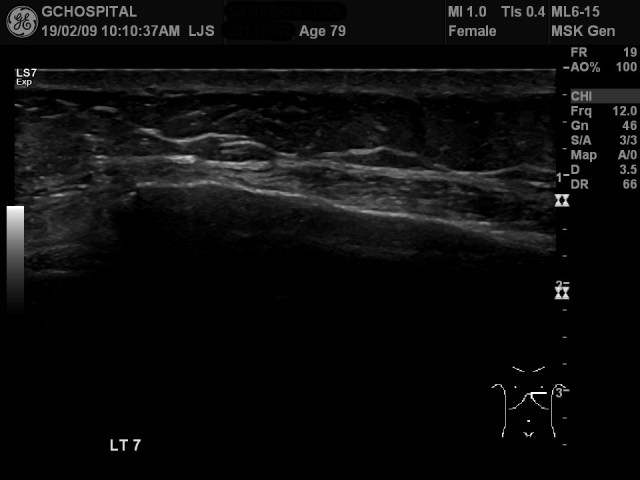

왼쪽 7번째 늑골에서는 피골의 불연속성이 희미해서 금방 골절을 확인하기 어려웠습니다. 하지만, 해당 부위에서 환자의 압통이 심했던 데다, 힘을 주면 늑골 모양이 angular deformity를 보였기 때문에 골절로 확인할 수 있었습니다.

교훈3. 또한, 항상 의심스러운 부위에서 탐촉자로 눌러보면서 환자가 압통을 느끼는지, 늑골의 윤곽이 압력에 의해 변형되는지 여부를 확인하는 dynamic study가 꼭 필요합니다. 이번 사례에서 일곱번째 늑골골절의 경우, 위 영상처럼 영상 자체만 가지고선 늑골 골절 여부를 확인하는게 불가능한 경우들이 정말 많습니다. 초음파영상이 다른 영상에 비해 가지고 있는 특장점이 쉽게 움직임을 확인할 수 있다는 점입니다. 적극적으로 활용해야만 검사의 민감도를 향상시킬 수 있습니다.